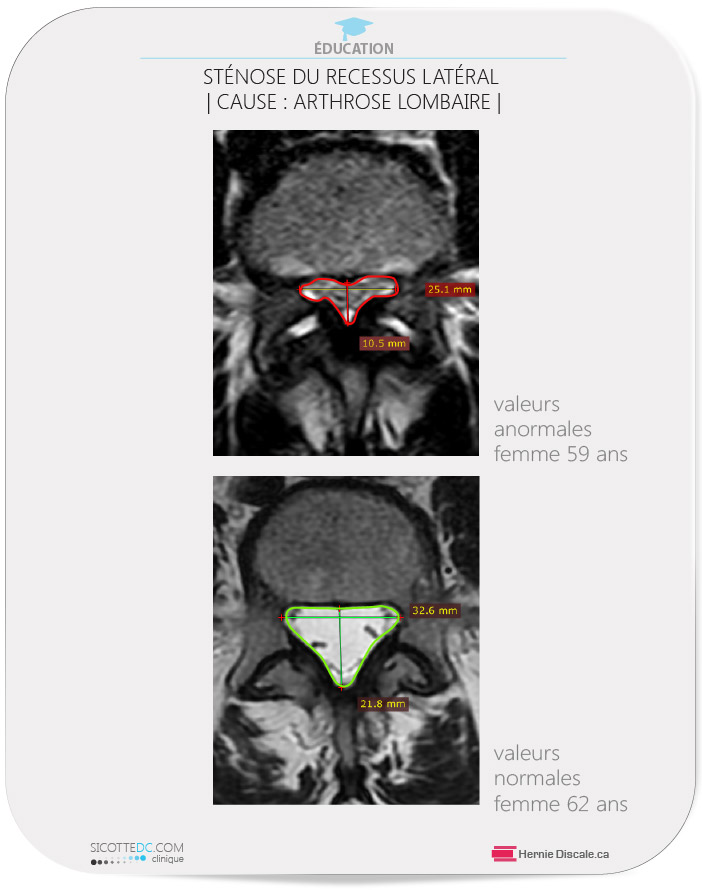

- rétrécit (sténose) le récessus latéral (*4),

STÉNOSE DU RÉCESSUS LATÉRAL| CAUSE DE l’ARTHROSE LOMBAIRE | (*4)